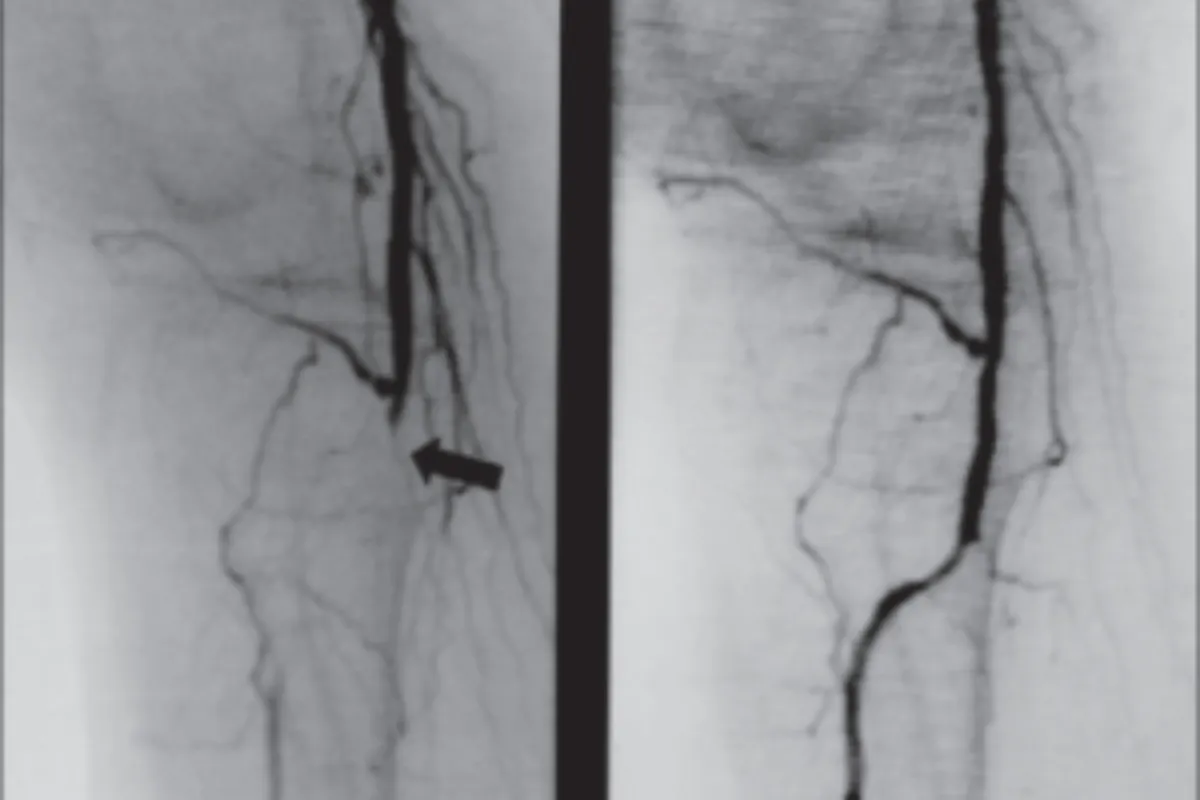

Interventional Radiology (IR) uses real-time imaging such as X-ray, ultrasound, CT, or MRI to guide tiny instruments through the body for treatment — without large surgical incisions.

Case's Video Gallery

Video Gallery